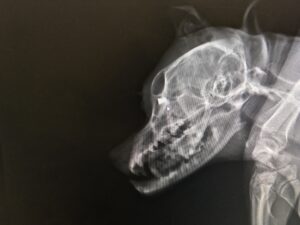

Utána rohanás az állatorvoshoz, a röntgenen egyből ott volt a bizonyíték is: a jobb szemgolyó mögött egy légpuska lövedék. Az állat szemét átlőve állt meg benne. Sajnos a jobb szemét el kellett távolítani. A rendőrségi feljelentés megtörtént, majd a szomszédnál házkutatás a fegyver után (mely sosem lett meg), nálam pedig a kamera felvétel lefoglalása.